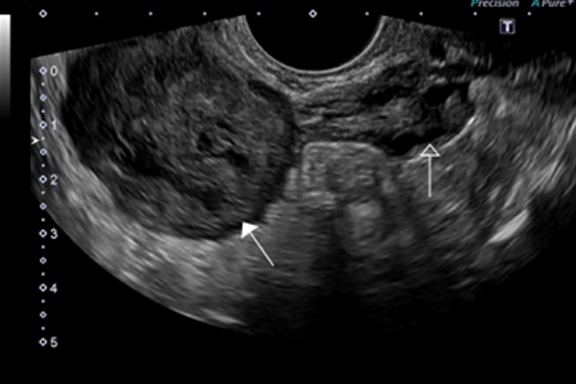

Fibroids grow in different parts of the uterus, and they are named according to which part of the uterus they are found. Chances of healing, childbearing and shrinking may also depend on the area of the womb that they are situated.

Fibroids that grow inside the wall of the uterus and found within the walls are called intramural fibroids, which by far is one of the most common types of fibroids.

There are some of these fibroids that grow outward from the wall of the uterus into the abdominal cavity. This type of fibroid is called Subserous or Suberosal fibroids. (See picture).

Those that grow inward from the uterine wall, taking up spaces outside the cavity of the uterus are called Submucous or Submucosal fibroids.

A fibroid that is attached to the uterus by a thick stalk is called pedunculated fibroid.